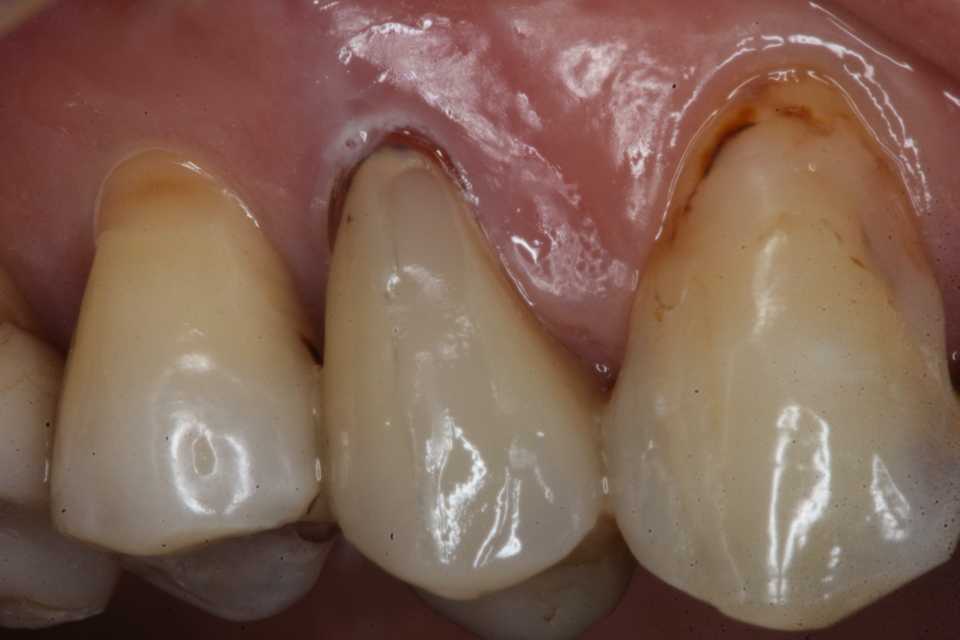

40代女性、右上4、Per+GAPerというのは根管治療後に根管内に感染を起こしている状態でGAとは炎症が根管の外に波及している状態。この方は10年程前に神経を取って被せたということでしたが、2、3年前GAができて別の歯医者に行ったら切って膿を出してもらったら治ったということでしたが、根管に細菌が感染している以上細菌が消えたりしないので、何度も再発します。今回は切開というよりは根管内部に3MIX+α-TCPを入れて根管内部を消毒殺菌しようというコンセプト。内部のポストも根管充填材も完全に除去する必要はない。根管充填材が見えるところまで穴を開けて薬剤を入れ、CRで蓋をするだけでよい。信じられないだろうが、これだけで治る。もし再発するようなら、冠のどこかに隙間があり、そこから細菌が出たり入ったりしているわけだから、冠もポストも除去して隙間を塞ぐ必要がある。多分従来の根幹治療しか知らない歯科医師は何が起こっているのか分からないと思うが、根管治療の真実が分かれば理解できないことはないと思う。一般に思われてる根管治療というのは理想からは程遠いものだということだ。冠にもポストにも根管充填材にも隙間だらけで細菌がその隙間から出入りしているのが現実だ。

では時系列でどうぞ